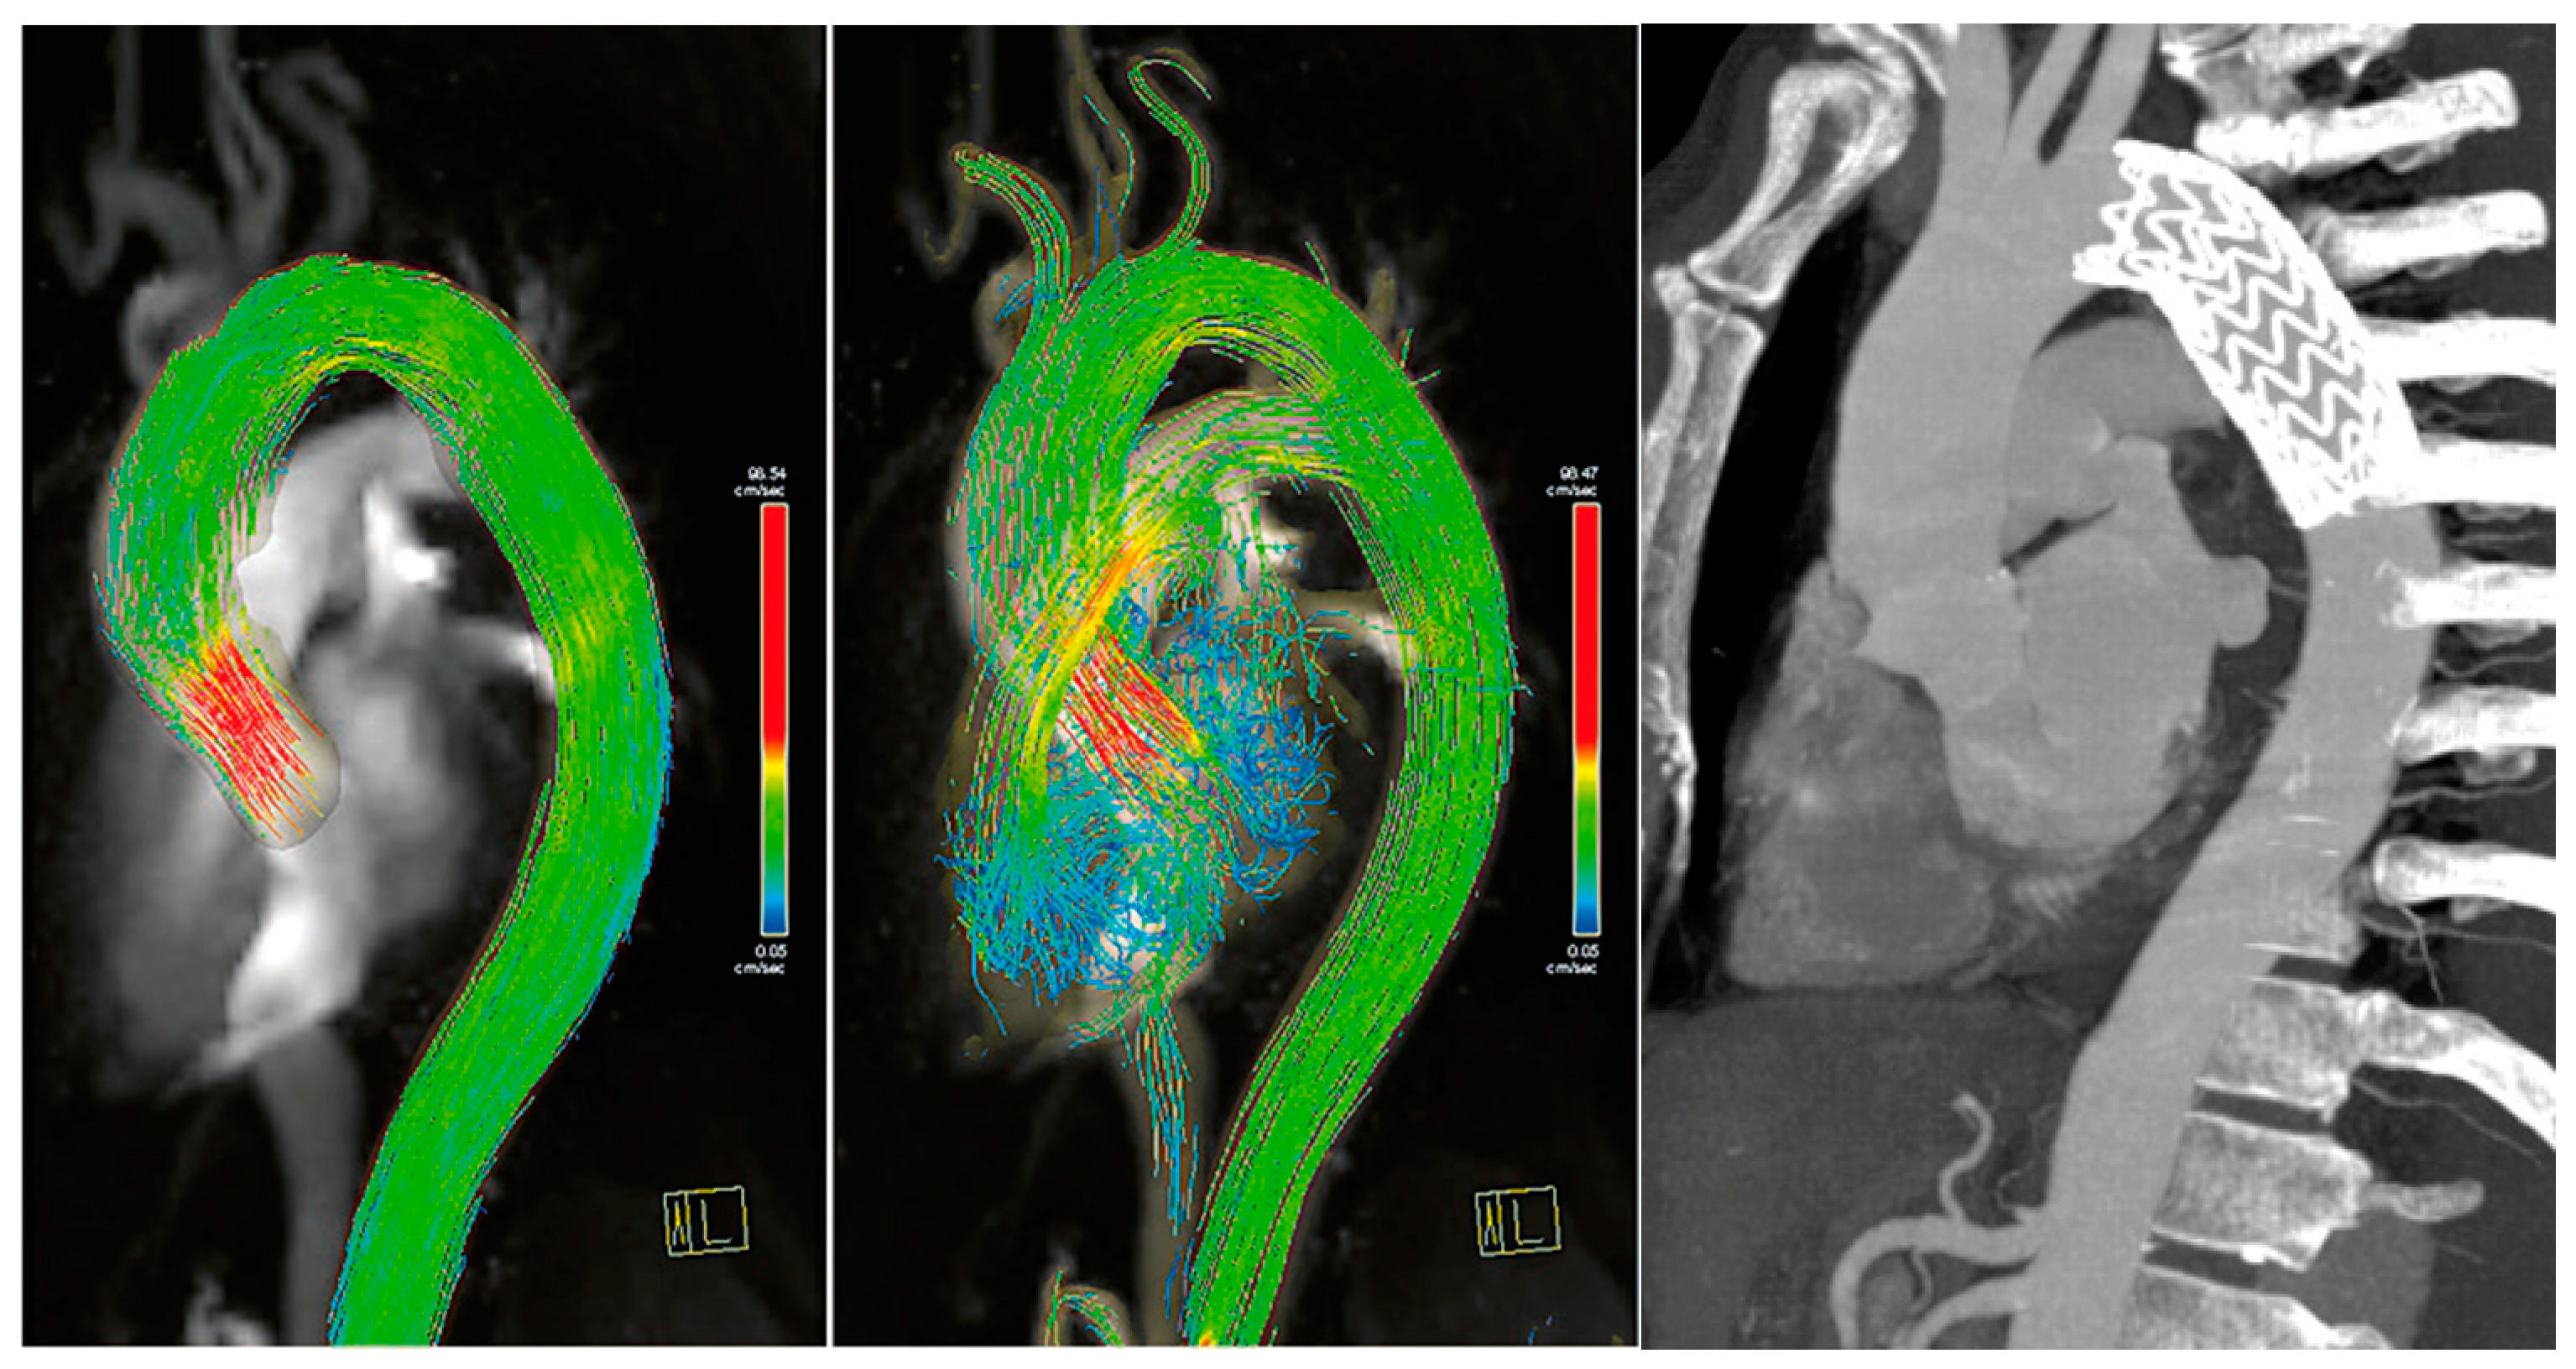

Four-Dimensional Flow MRI for the Evaluation of Aortic Endovascular Graft: A Pilot Study

3. Results

| Flow Rate mL/Beat | p Value | |

|---|---|---|

| A1 | 75 (47–93) | 0.043 (A1 vs. A2) |

| A2 | 54 (40–59) | 0.326 (A2 vs. A3) |

| A3 | 50 (35–55) | 0.044 (A1 vs. A3) |